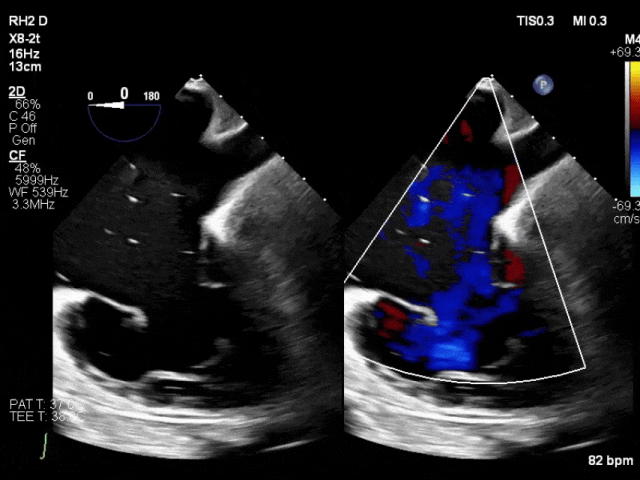

69岁女性,既往有房颤病史、4年前接受A型主动脉夹层修复术,3年前因重度二尖瓣反流(MR)及三尖瓣反流(TR)行经导管缘对缘修复术(TEER),此次因心衰管理问题就诊寻求第二诊疗意见。

二尖瓣修复效果持久稳定,但TR因发生单侧瓣叶装置附着(SLDA)于术后短期内复发为极重度反流。尽管强化药物治疗,症状仍持续恶化,遂考虑TR再次干预。

虽患者相对年轻,但心脏团队评估认为其因既往手术史及衰弱状态属外科高危。经导管方案中,因存在较大对合间隙及原发性瓣叶退变,再次TEER不可行,故TTVR成为唯一选择。前叶脱落的夹子对依赖瓣叶锚定的EVOQUE瓣膜植入构成挑战——该夹子可能阻碍锚定件进入瓣叶后方并影响成像。但由于脱落夹子靠近前隔联合处,研判其可为输送系统操作及瓣膜释放保留中央区足够空间。术中对锚定件与TEER装置的相对位置进行精确定位评估,最终锚定件分列装置两侧无空间冲突,且无瓣周漏。1年随访时患者自述"重获新生",未再出现心衰症状。